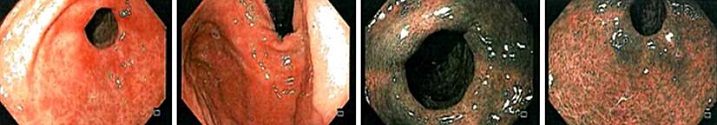

Se realiza una nueva esofagogastroduodenoscopia con biopsia de mucosa corporal, antral y esófago en la que se encuentra una gastritis crónica atrófica con extensa metaplasia pseudopilórica (antralización) y actividad moderada en la mucosa corporal (oxíntica), asociada con hiperplasia lineal y nodular de células neuroendocrinas (enterocromafines); esto último resaltado con el estudio de inmunohistoquímica para cromogranina (Figura 1). Mientras que en la mucosa antral se observó una gastritis crónica no atrófica leve, con agregados linfoides residuales, sin actividad inflamatoria aguda y sin evidencia de bacilos con morfología de Helicobacter pylori. Los hallazgos de una gastritis crónica atrófica restringida a la mucosa oxíntica, con hiperplasia de células neuroendocrinas (enterocromafines) son sugestivos de una gastritis autoinmune. Adicionalmente, a nivel esofágico, se documentó infección compatible con Candida sp. En consecuencia, a los hallazgos histológicos se completó el perfil autoinmune, se ajustó el manejo médico y finalmente se hizo el diagnóstico de gastritis autoinmune dada la presencia de anticuerpos anticélulas parietales positivos.

En los controles posteriores fue necesaria la reposición con hierro endovenoso en una ocasión. Actualmente, el paciente se encuentra sin requerimiento de manejo médico. La última esofagogastroduodenoscopia de control (Figura 2) evidenció la presencia de gastritis eritematosa corporoantral, cuyas biopsias mostraron una disminución en la marcación de gastrina, lo que corresponde al diagnóstico ya conocido, con paraclínicos dentro de límites normales.